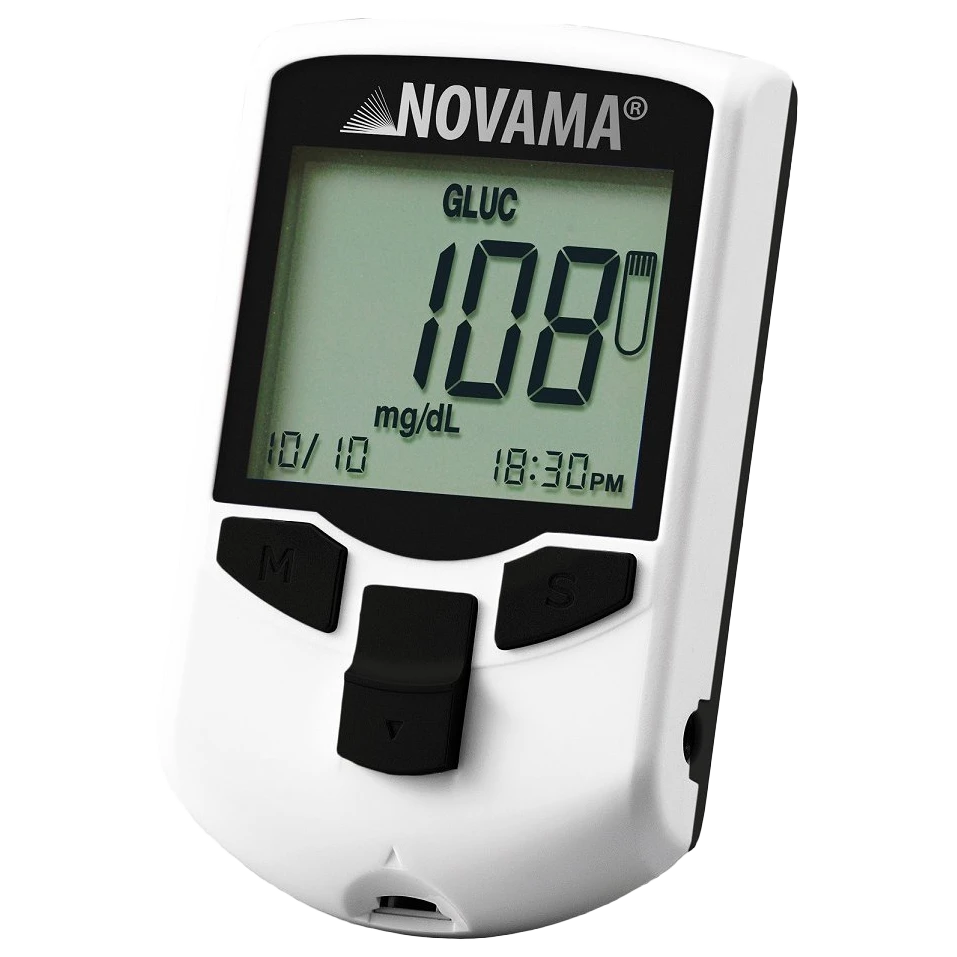

PULSOKSYMETR

Pulsoksymetr to niewielkie, elektroniczne urządzenie medyczne umożliwiające przezskórny, nieinwazyjny i bezbolesny pomiar wysycenia krwi tętniczej tlenem (saturacji – SpO₂) oraz częstotliwości pracy serca (pulsu, PRbpm).

Dzięki zastosowaniu dwóch długości fal świetlnych aparat odróżnia oksyhemoglobinę od hemoglobiny pozbawionej tlenu, co pozwala na szybkie i wiarygodne oszacowanie stanu utlenowania organizmu bez konieczności pobierania krwi.

W nowocześniejszych modelach możliwe jest również wykrycie obecności methemoglobiny czy karboksyhemoglobiny, które mogą wpływać na ostateczny wynik saturacji (4).

Pierwotnie pulsoksymetry stosowano głównie w placówkach medycznych na oddziałach szpitalnych, w gabinetach ambulatoryjnych oraz w ratownictwie. Wraz z pandemią COVID-19 ich popularność gwałtownie wzrosła, a urządzenia te zaczęto powszechnie wykorzystywać także w warunkach domowych, co umożliwia pacjentom samodzielną kontrolę parametrów życiowych (5,6).